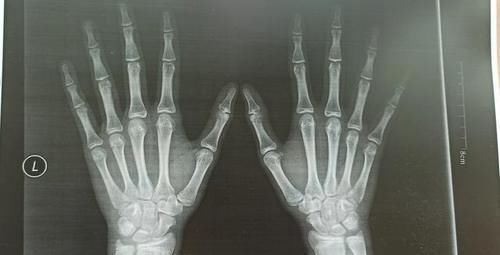

现在我家孩子15岁半了,身高只有167cm,体重49公斤。感觉好几个月都没怎么长高。去医院拍了骨龄照,结果不是很理想。

文章插图

这种情况应该没有什么长高的空间了。有点后悔当初自行停药,应该给孩子再接着打生长激素的。但是没有后悔药吃。